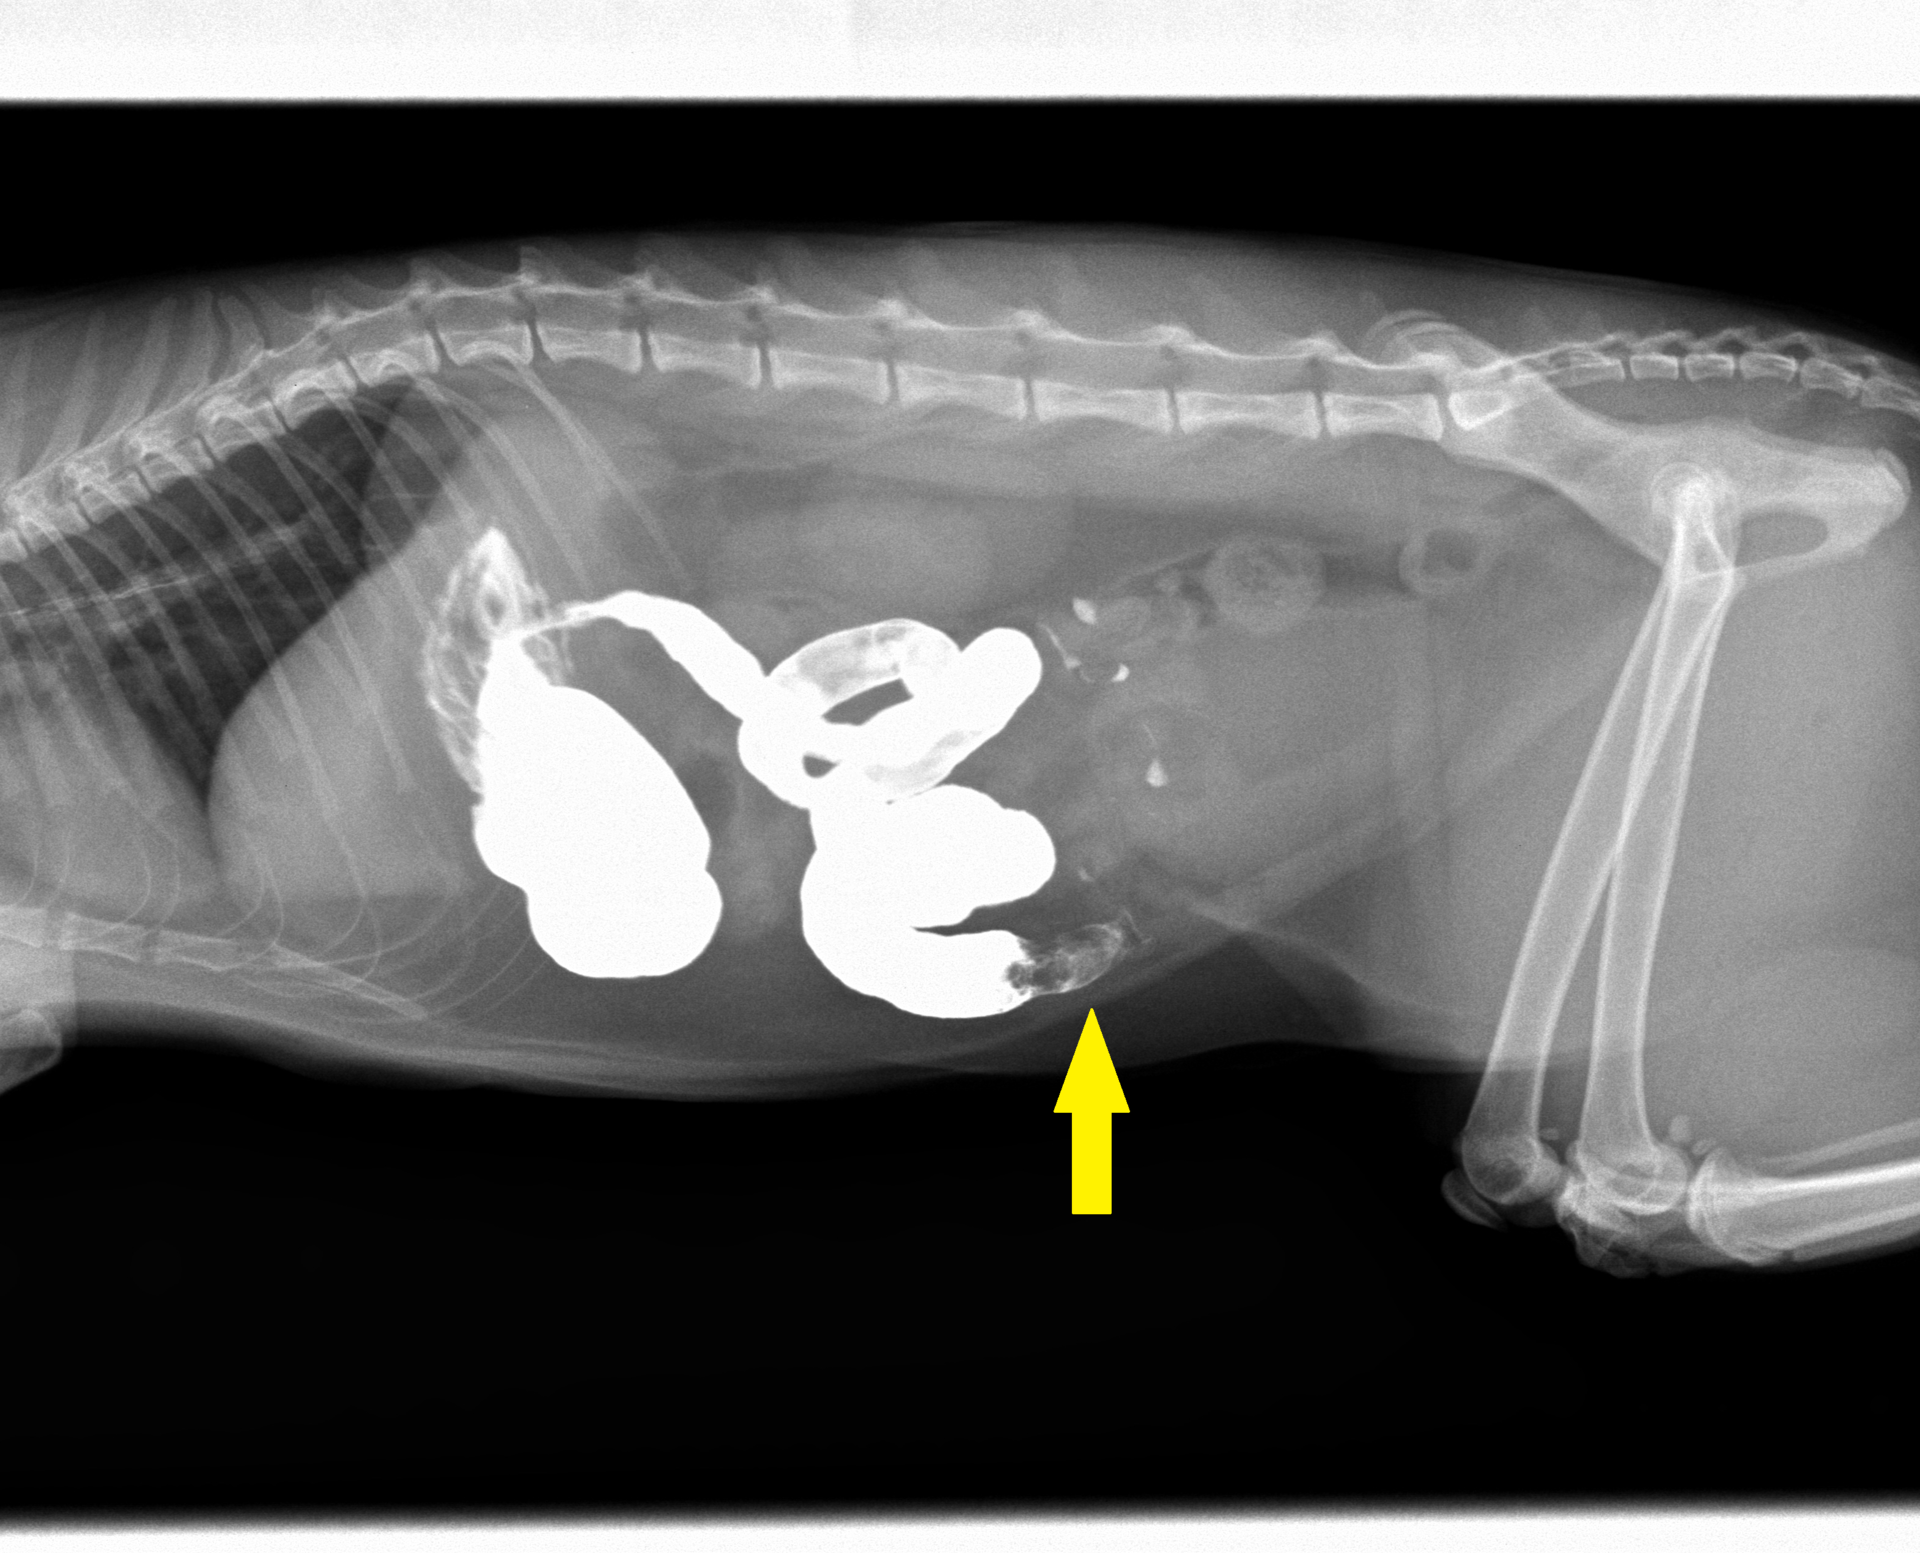

今回は、猫ちゃんの異物による腸閉塞です。症例の猫ちゃんは2歳の雄(去勢済)で、ある日食欲がなく、吐くということで来院されました。普段から紐や靴などを噛んで遊んでいるということだったので、レントゲンを撮りました。それが下の写真です。見た限りは特に異常は見当たりませんでした。